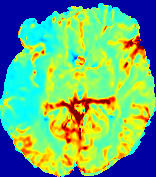

4.3.1 Advection Imaging via Advection-Diffusion

Slice #1Slice #2Slice #3Slice #4Slice #5Slice #6𝐕gt𝟐subscriptnormsuperscript𝐕gt2\|\bf{V}^{\text{gt}}\|_{2}Refer to captionRefer to captionRefer to captionRefer to captionRefer to captionRefer to caption𝐕est𝟐subscriptnormsuperscript𝐕est2\|\bf{V}^{\text{est}}\|_{2}Refer to captionRefer to captionRefer to captionRefer to captionRefer to captionRefer to captionRefer to caption1.51.51.51.21.21.20.90.90.90.60.60.60.30.30.30.00.00.0(mm/s)𝑚𝑚𝑠(mm/s)Destsuperscript𝐷estD^{\text{est}}Refer to captionRefer to captionRefer to captionRefer to captionRefer to captionRefer to captionRefer to caption0.0150.0150.0150.0120.0120.0120.0090.0090.0090.0060.0060.0060.0030.0030.0030.0000.0000.000(mm2/s)𝑚superscript𝑚2𝑠(mm^{2}/s)

Figure 14: PIANO identifiability testing: advection imaging via advection-diffusion. Top row shows 𝐕gt2subscriptnormsuperscript𝐕gt2\|{\bf{V}}^{\text{gt}}\|_{2} used for simulating ground truth pure advection. Rows below show the estimated 𝐕est2subscriptnormsuperscript𝐕est2\|{\bf{V}}^{\text{est}}\|_{2} and Destsuperscript𝐷estD^{\text{est}} on corresponding slices. Note that the plotted value scale for Destsuperscript𝐷estD^{\text{est}} is 0.01 of that for 𝐕gt2subscriptnormsuperscript𝐕gt2\|{\bf{V}}^{\text{gt}}\|_{2} and 𝐕est2subscriptnormsuperscript𝐕est2\|{\bf{V}}^{\text{est}}\|_{2}.

We use the same ‘Advection Imaging’ simulation of Sec. 4.2.1 as the concentration dataset for PIANO. However, instead of modeling pure advection (Eq. 15), we let PIANO estimate both velocity 𝐕estsuperscript𝐕est{\bf{V}}^{\text{est}} and diffusivity Destsuperscript𝐷estD^{\text{est}} via the advection-diffusion PDE (Eq. 2) underlying the proposed PIANO model. Fig. 14 shows the estimated 𝐕est2,subscriptnormsuperscript𝐕est2\|{\bf{V}}^{\text{est}}\|_{2}, and Destsuperscript𝐷estD^{\text{est}} fields for one patient. Although PIANO has the freedom to estimate both a velocity and a diffusivity field from pure advection, PIANO differentiates well between advection and diffusion: the estimated 𝐕est2subscriptnormsuperscript𝐕est2\|{\bf{V}}^{\text{est}}\|_{2} successfully reproduces the ground truth 𝐕gt2subscriptnormsuperscript𝐕gt2\|{\bf{V}}^{\text{gt}}\|_{2} governing the simulated advection process, just as it already did in the ‘Advection Imaging via Advection’ test (Fig. 12). More importantly, the estimated diffusivity Destsuperscript𝐷estD^{\text{est}} is orders of magnitudes smaller than 𝐕est2subscriptnormsuperscript𝐕est2\|{\bf{V}}^{\text{est}}\|_{2}, indicating the estimated diffusion is negligible compared to the estimated advection, which is highly consistent with the underlying pure advection of the simulated data.